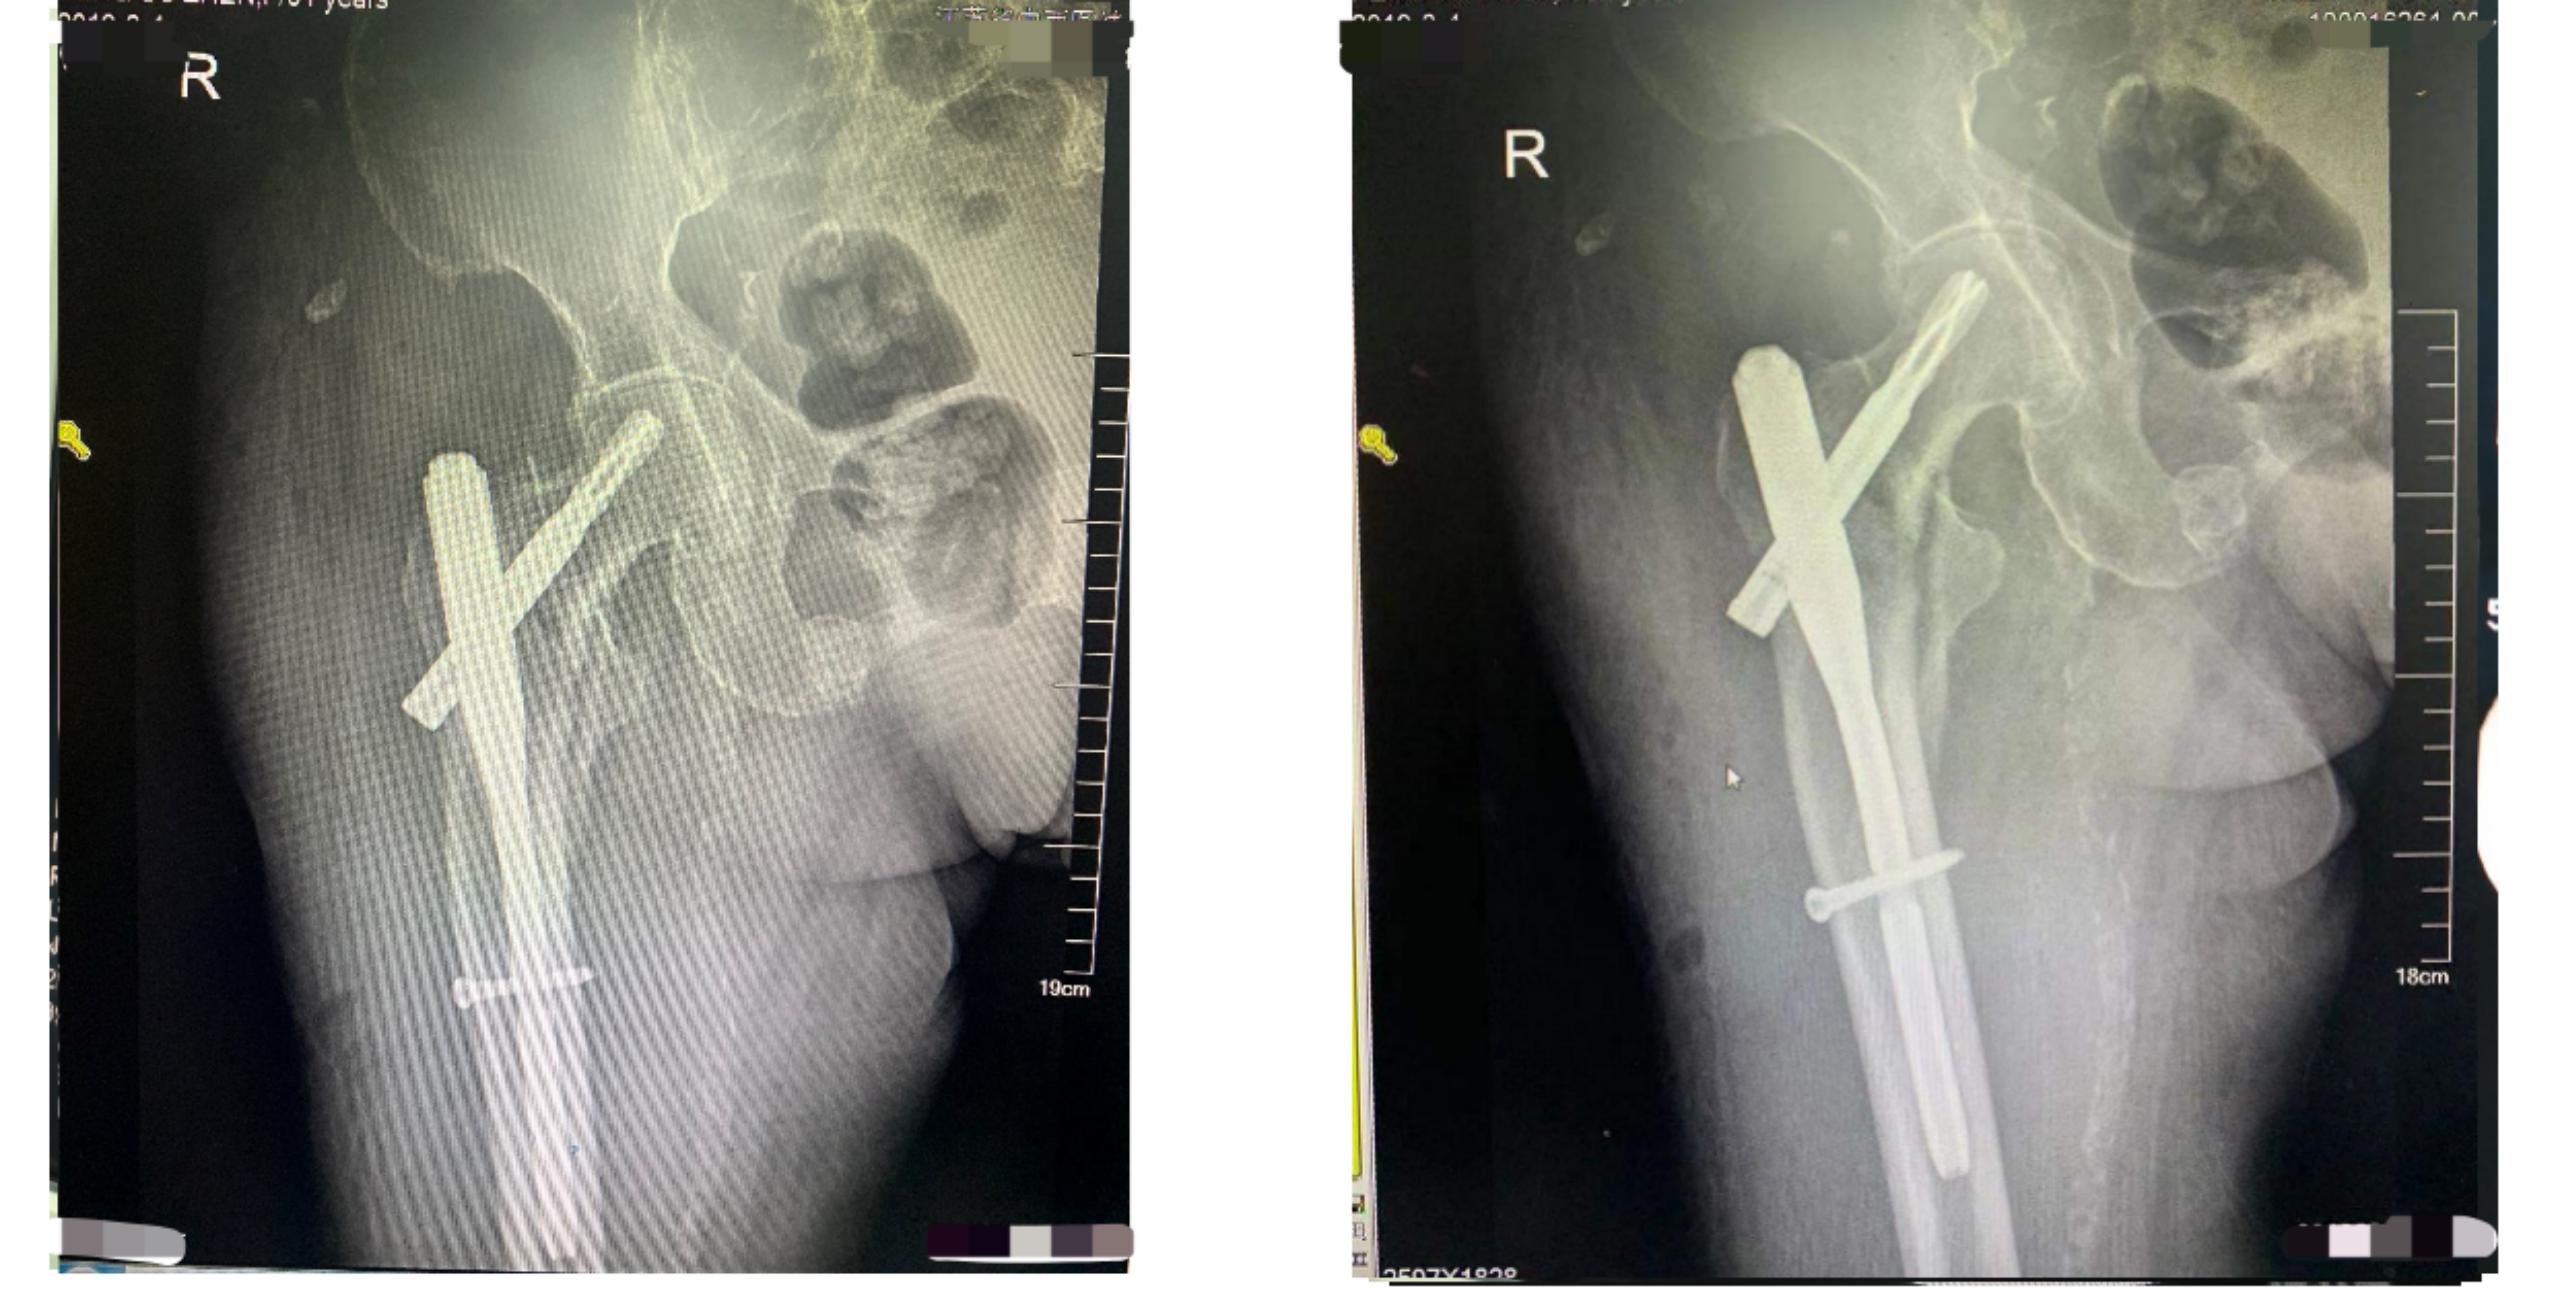

经过详细的检查,老人患有贫血、低蛋白血症、双肺气肿、心房颤动等基础疾病,因此普通手术治疗的风险比较大,需要采用防旋型股骨近端髓内钉(PFNA)内固定术进行治疗。